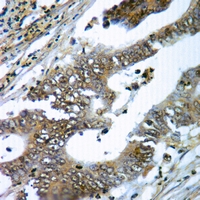

Immunohistochemical analysis of gp91 phox staining in human colorectal cancer formalin fixed paraffin embedded tissue section. The section was pre-treated using heat mediated antigen retrieval with sodium citrate buffer (pH 6.0). The section was then incubated with the antibody at room temperature and detected using an HRP conjugated compact polymer system. DAB was used as the chromogen. The section was then counterstained with haematoxylin and mounted with DPX.